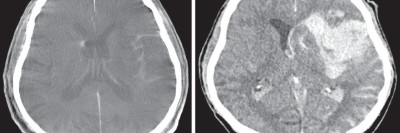

Komplikation bei mechanischer Thrombektomie? So gehen Sie vor

Die gefürchtetste Komplikation im Rahmen der mechanischen Thrombektomie ist das Auftreten von (symptomatischen) intrazerebralen Blutungen. In diesem Übersichtsartikel wird ein Überblick über diese und andere im Rahmen einer mechanischen Thrombektomie auftretenden Komplikationen gegeben.

Magnetresonanztomographie/© Svitlana / Stock.adobe.com (Symbolbild mit Fotomodell), Schaumiges Bronchialsekret bei akutem Lungenödem/© Eichner M. doi.org/10.1007/s00063-025-01258-9 unter CC-BY 4.0, Intrazerebrale Blutung nach mechanischer Thrombektomie/© Mohamad J / all rights reserved Springer Medizin Verlag GmbH, Intrakranielle Abszesse/© Seidl H et al. doi.org/10.1007/s00108-025-01863-y unter CC-BY 4.0, Bildtitel/© Klaus Eppele / stock.adobe.com (Symbolbild mit Fotomodell), Seniorin liegt reglos auf Boden/© Racle Fotodesign / stock.adobe.com (Symbolbild mit Fotomodell), Tumor im linken Kleinhirnbrückenwinkel und inneren Gehörgang (linkes Bild) und Tumor am Foramen jugulare (rechtes Bild)/© Springer Medizin, Eine Frau im MRT/© Maksym Povozniuk / stock.adobe.com (Symbolbild mit Fotomodellen), Passantin hilf Frau, die bewusstlos am Boden liegt/© M.Dörr & M.Frommherz / stock.adobe.com (Symbolbild mit Fotomodellen), CT-Aufnahme bei intrakranieller Hämorrhagie/© stockdevil / Fotolia, CT und MRT bei Schädel-Hirn-Trauma/© Springer Medizin Verlag GmbH, Junger Mann liegt auf CT-Liege/© LStockStudio / stock.adobe.com (Symbolbild mit Fotomodell), Lesion in the right-sided medial occipitotemporal gyrus/© Springer-Verlag GmbH, Frau bei Strahlentherapie/© (M) Mark Kostich / Stock.adobe.com (Symbolbild mit Fotomodellen), Search Icon, CT-Pulmonalisangiographie/© Das M et al. doi.org/10.1007/s00117-016-0100-3 unter CC-BY 4.0, Kanüle für Katheterbehandlung/© romaset / stock.adobe.com, Alter Mann in Sprechstunde mit junger Ärztin/© lordn / Stock.adobe.com (Symbolbild mit Fotomodellen)